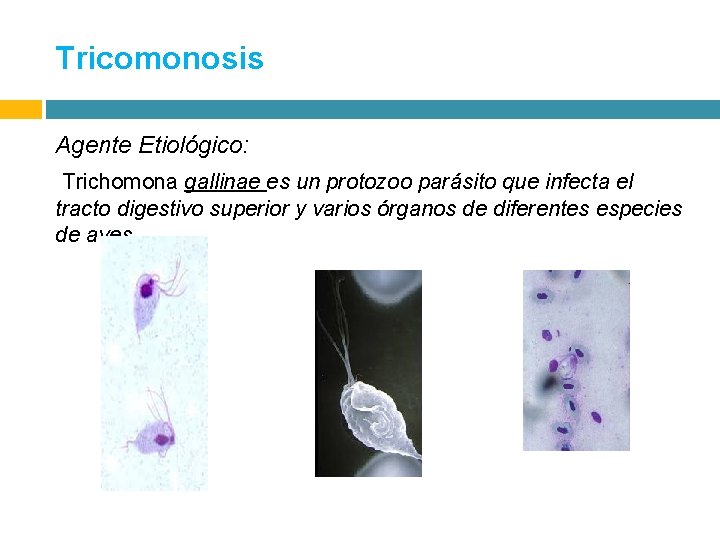

Tricomonosis Agente Etiológico: Trichomona gallinae es un protozoo parásito que infecta el tracto digestivo superior y varios órganos de diferentes especies de aves.